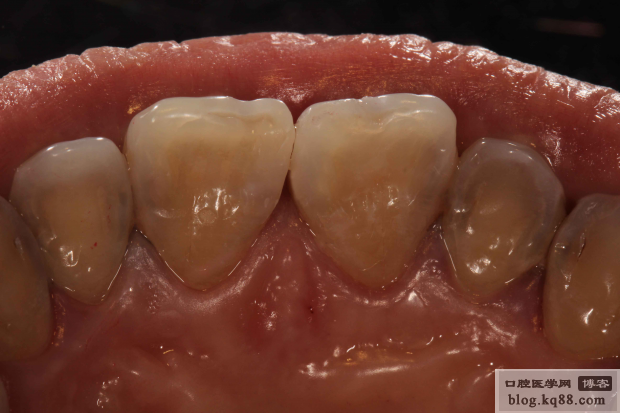

術(shù)前

充填完成